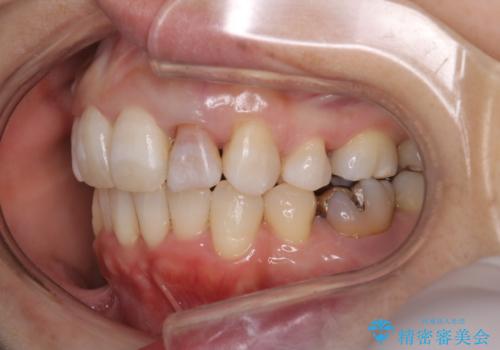

重度のガタガタと出っ歯をワイヤーによる抜歯矯正で整った歯並びへ

- 全体的ながたがたを主訴に来院されました。

上顎の前歯は前方に傾斜して、下顎の前歯は強いガタガタが見られました。

前から4番目の歯を上下左右合計2本抜歯して、歯並びを整える計画としました。